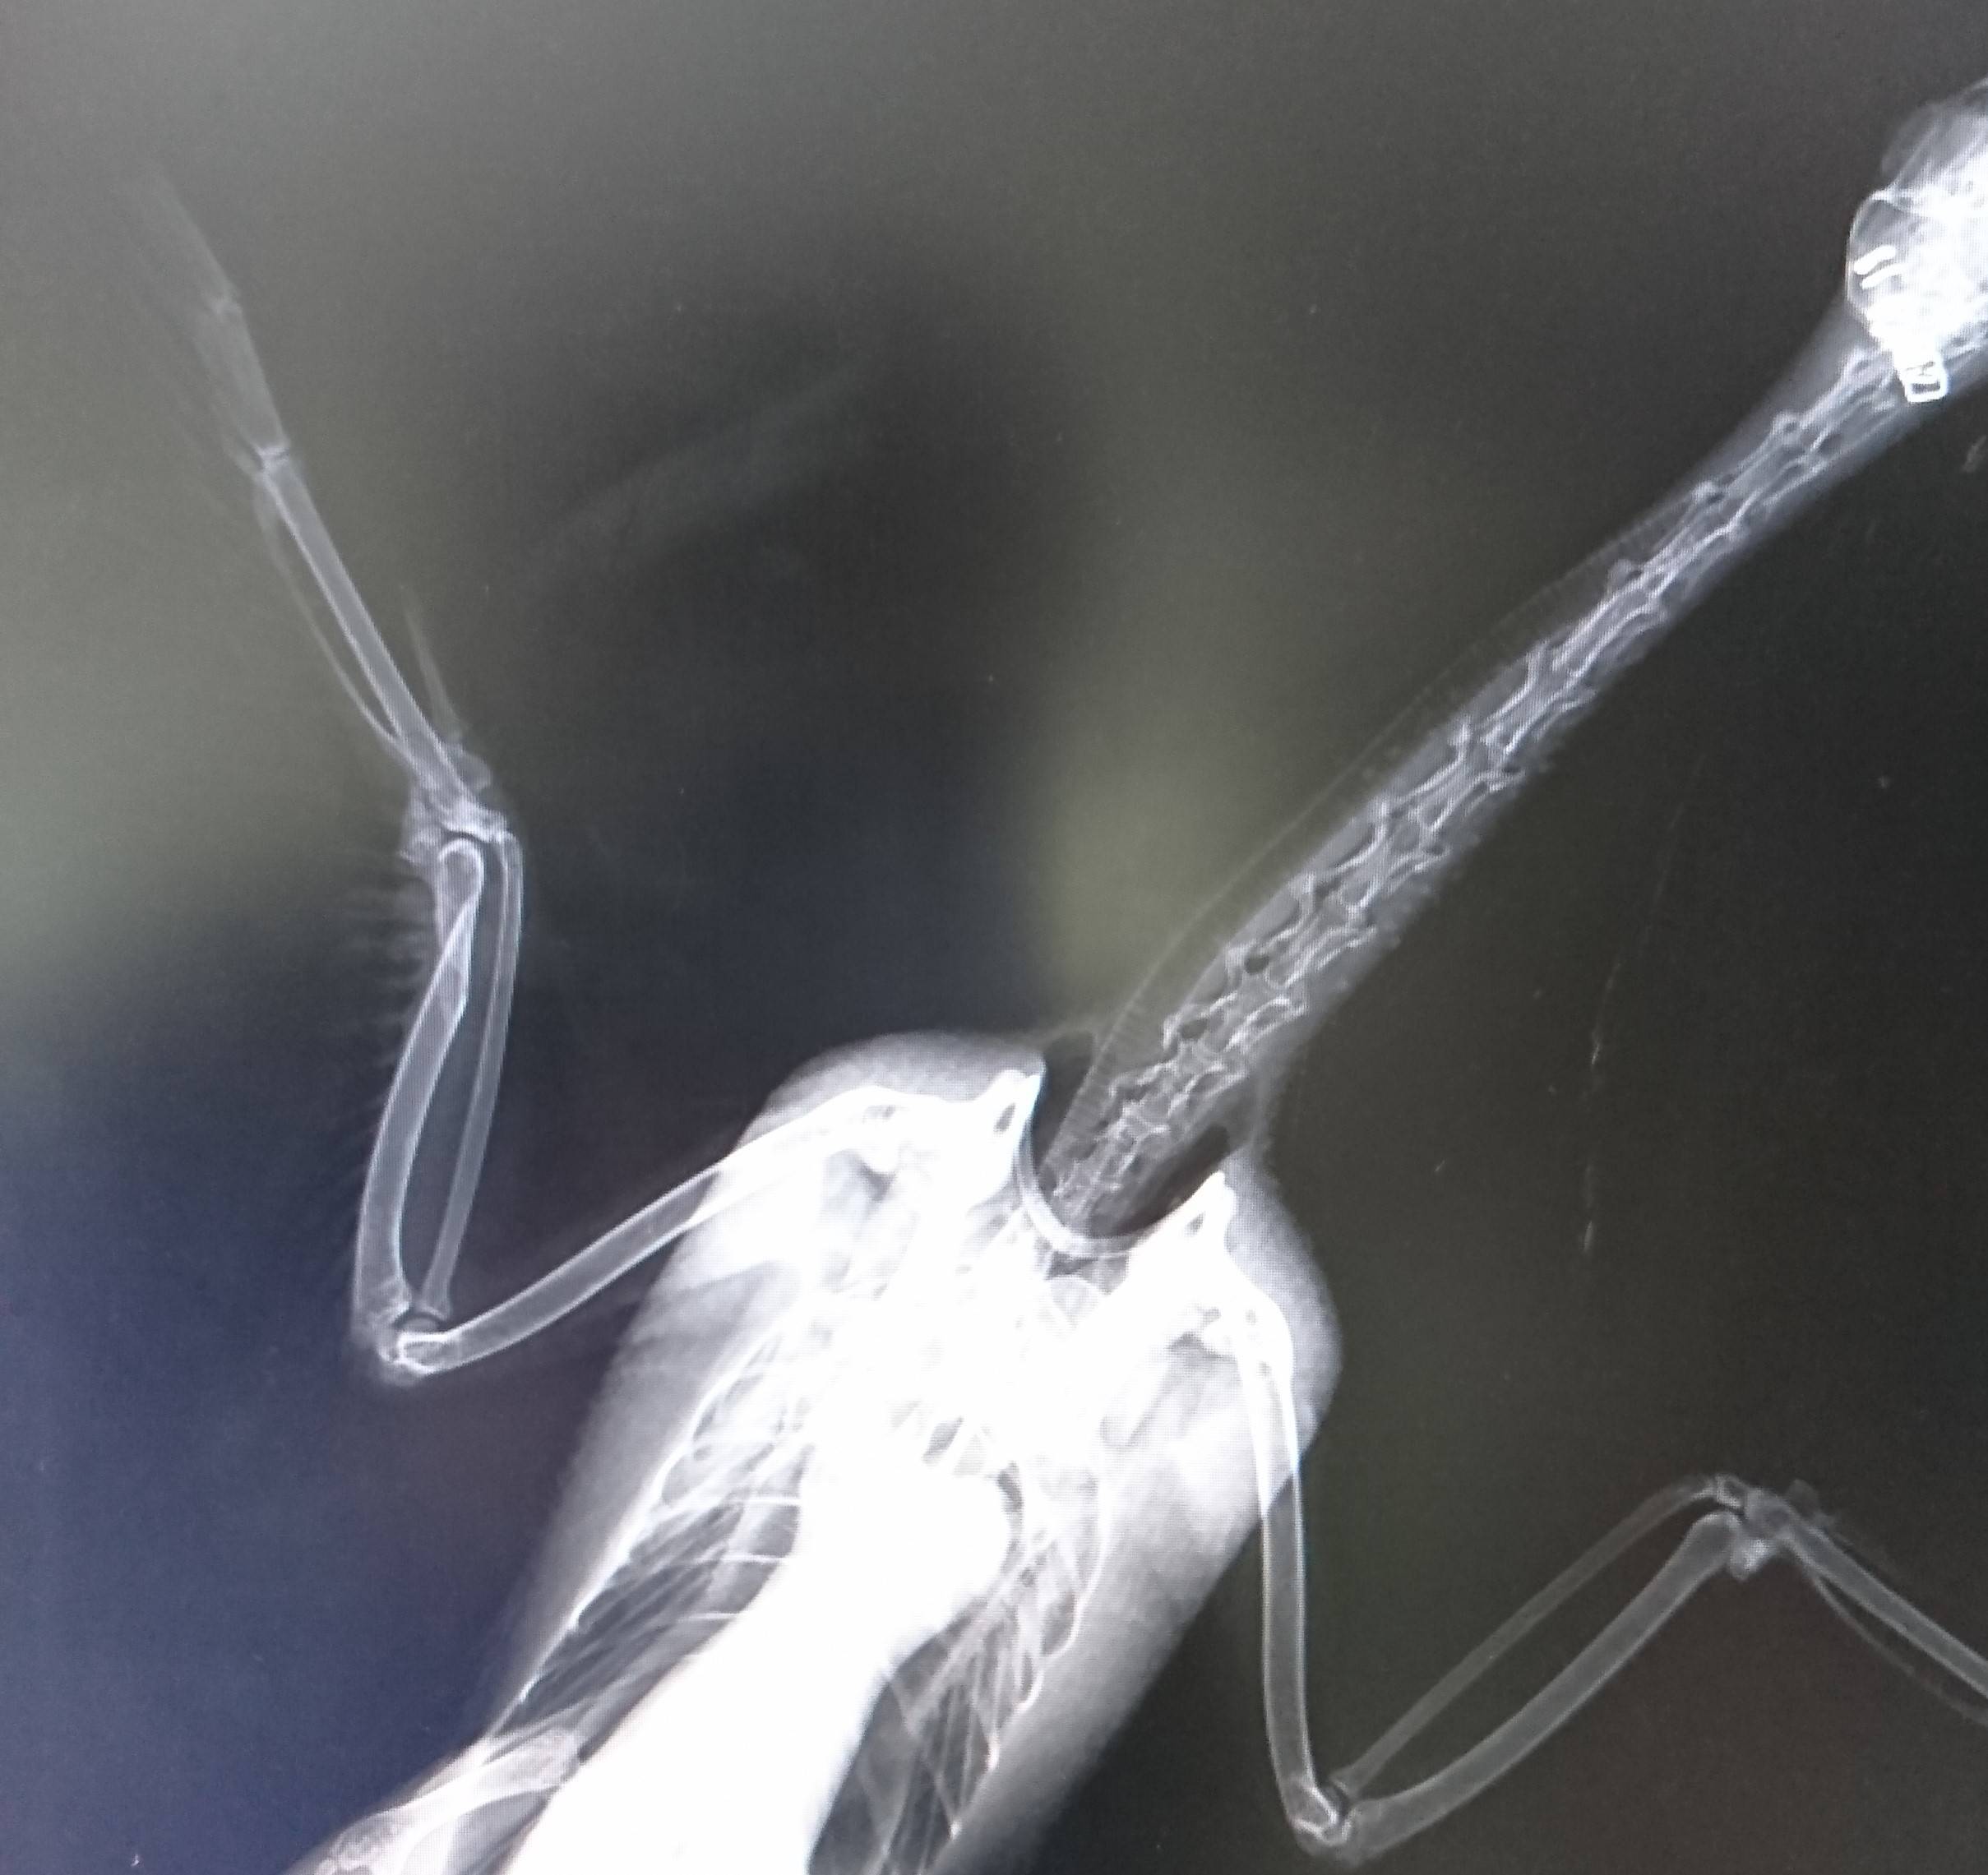

こちらがその時のレントゲン画像です。

右の翼の骨が折れてしまっています。